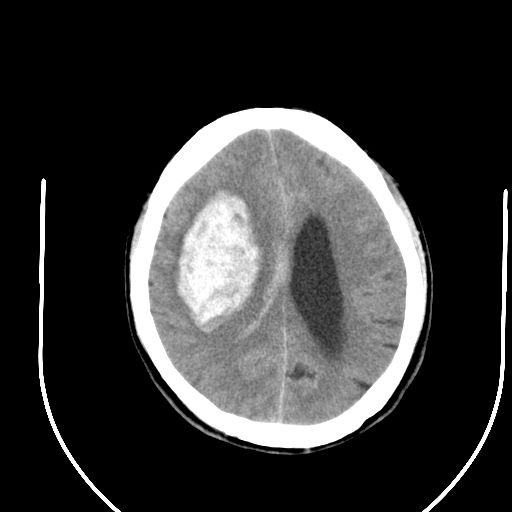

标题: CT24997:M,60Y,突发昏迷30分钟,有高血压病史。 [打印本页]

标题: CT24997:M,60Y,突发昏迷30分钟,有高血压病史。

右侧基底节区脑出血并破溃入脑室。

支持楼主诊断,脑中线结构有偏移,脑疝形成可能!

1右侧基底节脑出血伴脑干出血并破入脑室系统脑疝形成2梗阻性脑积水

1)右侧基底节脑出血伴脑干出血并破入脑室系统。2)大脑镰下疝。3)梗阻性脑积水。

1、右侧基底节脑出血伴脑干出血并破入脑室系统。

2、大脑镰下疝。

3、梗阻性脑积水。